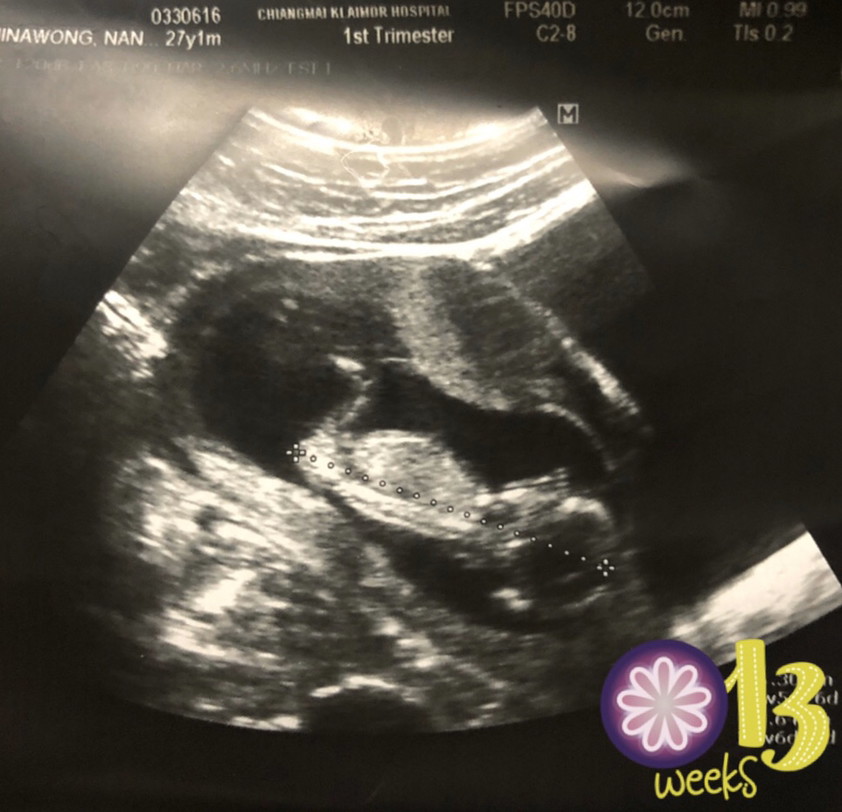

แม่ๆคนไหนมีภาพอัลตร้าซาวด์ประมาณ13วีคบ้างคะ ของเรา13วีค ภาพแบบนี้ค่ะ ดูไม่ออกเลย?

13week. จ้า❤

13weeksคร้า